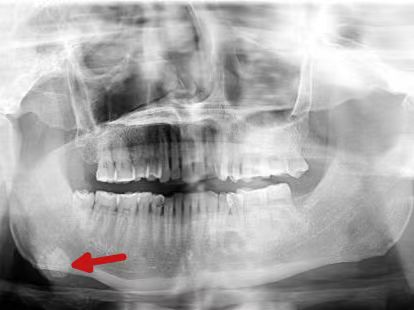

12-27 02:20...目前术后恢复良好,已顺利出院。好好的口腔里为什么会凭空长结石?这到底是种什么病?广东医科大学附属东莞松山湖中心医院(东莞市松山湖中心医院)口腔颌面外科主任医师姜刚勇为大家解答。什么是颌下腺导管结石病,颌下腺导管结石是怎么形成的?人体共有三对大唾液腺(腮腺、颌下腺、舌下腺)及若干分散的小腺体。其中,颌下腺位于下颌两侧,左... 0